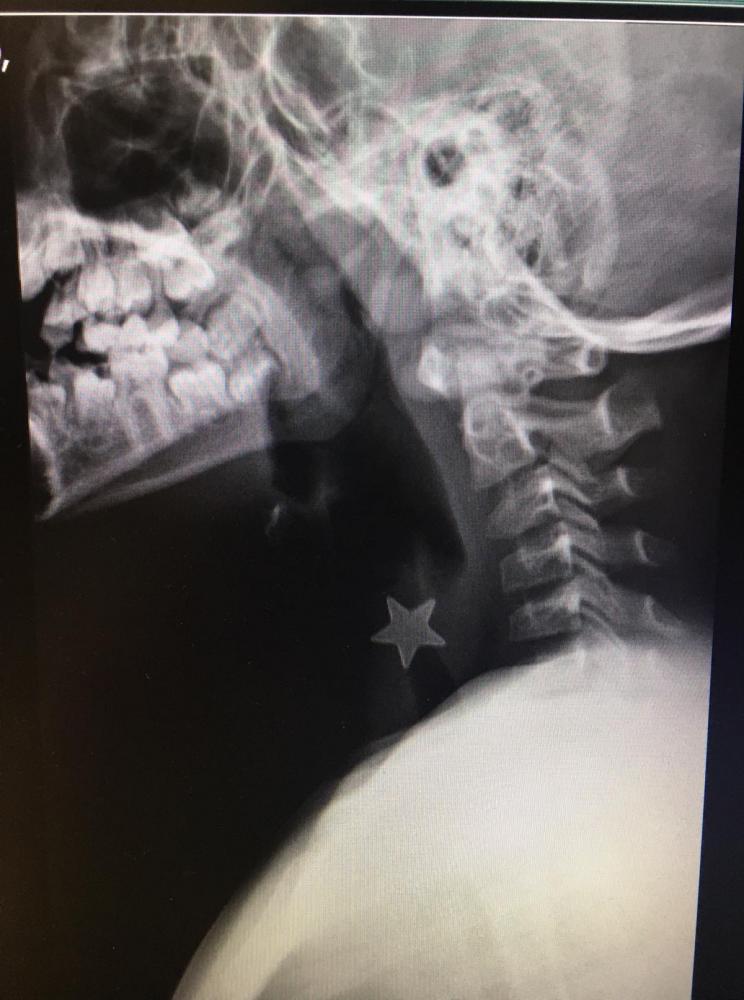

Una stellina di metallo del diametro di 1,5 centimetri ferma nella trachea e inalata da più di 24 ore. Si è presentato in questi condizioni un bambino di 8 anni a Niguarda, inviato nella notte con un trasporto d’urgenza da un altro ospedale milanese dedicato alle cure pediatriche. “Abbiamo deciso di intervenire nell’immediato, il piccolo infatti era gravemente asfittico nonostante la stellina fosse stata inalata da tempo, da circa un giorno- spiega Massimo Torre, Direttore della Chirurgia Toracica -. Non si poteva aspettare oltre, alle due della notte la sala operatoria e l’équipe erano pronti per la procedura di rimozione”.

Un’ora di intervento condotto attraverso un broncoscopio introdotto dalle vie aeree con 6 mm di diametro. “Attraverso questo strumento si inserisce una particolare pinza miniaturizzata con cui si va ad estrarre l’oggetto inalato – dice Serena Conforti, Responsabile della Chirurgia Endoscopica del Torace- . Si tratta di un’operazione molto delicata che richiede un alto grado di specializzazione per evitare danni alle strutture. In questi casi il corpo era posizionato nella parte alta della trachea appena sotto le corde vocali. Per i bambini più piccoli invece si utilizzano broncoscopi con un diametro di 3-4 millimetri, si tratta di cannule dello spessore di una penna con spazi di manovra ancora più limitati e nei casi più difficili i tempi di intervento possono allungarsi arrivando a superare anche le 3 ore. Le più insidiose da togliere sono le noccioline, spesso si frammentano e sono difficili da agganciare, a volte abbiamo bisogno di sagomarle con un laser endoscopico miniaturizzato per creare un appiglio per l’estrazione”.